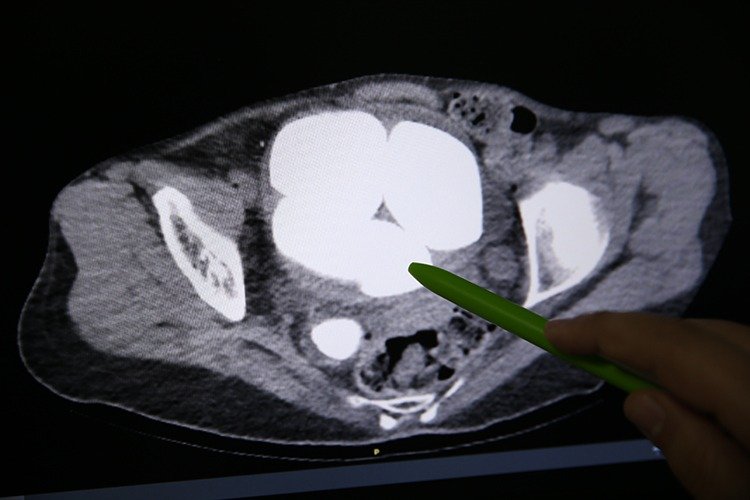

Üroloji Bölümünde Opr. Dr. Süleyman Çankaya tarafından yapılan tetkiklerde, hastanın mesanesi ve idrar kanalında en küçüğü 2, en büyüğü 9 santimetre olan 6 taş tespit edildi.

Bu rahatsızlığın sık olmasından dolayı tomografi de çekildiğini ifade eden Çankaya, "Tomografi sonucunda böbreklerin zarar gördüğünü, böbreklerde genişleme olduğunu tespit ettik. İdrar kesesinde büyük 5 taş olduğunu, sağ böbrek kanalında da idrar kesesine yakın kesiminde yine büyük bir taş bulunduğunu gördük. Hasta zihinsel engelli ve kendisini ifade edemiyor. Bu sonuç üzerine ameliyat kararı aldık." dedi.